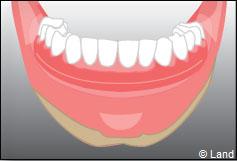

Les implants peuvent aussi servir à stabiliser un appareil amovible au maxillaire supérieur comme au maxillaire inférieur. Dans ce cas, les implants retiennent la prothèse amovible par des systèmes d’attachement.

Deux techniques sont possibles. Elles font appel à la barre de rétention ou aux boutons-pressions.

Exemple d’une réhabilitation complète implantaire

Situation clinique initiale

Situation clinique terminée